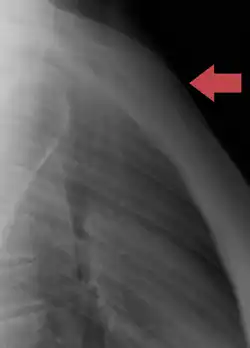

Figure 4 Ossification

Figure 6 Peculiarities

Figure 7

The sternum develops from two cartilaginous bars one on the left and one on the right, connected with the cartilages of the ribs on each side.[6] These two bars fuse together along the middle to form the cartilaginous sternum which is ossified from six centers: one for the manubrium, four for the body, and one for the xiphoid process.

The ossification centers appear in the intervals between the articular depressions for the costal cartilages, in the following order: in the manubrium and first piece of the body, during the sixth month of fetal life; in the second and third pieces of the body, during the seventh month of fetal life; in its fourth piece, during the first year after birth; and in the xiphoid process, between the fifth and eighteenth years.

The centers make their appearance at the upper parts of the segments, and proceed gradually downward. To these may be added the occasional existence of two small episternal centers, which make their appearance one on either side of the jugular notch; they are probably vestiges of the episternal bone of the monotremata and lizards.

Occasionally some of the segments are formed from more than one center, the number and position of which vary [Fig. 6]. Thus, the first piece may have two, three, or even six centers.

When two are present, they are generally situated one above the other, the upper being the larger; the second piece has seldom more than one; the third, fourth, and fifth pieces are often formed from two centers placed laterally, the irregular union of which explains the rare occurrence of the sternal foramen [Fig. 7], or of the vertical fissure which occasionally intersects this part of the bone constituting the malformation known as fissura sterni; these conditions are further explained by the manner in which the cartilaginous sternum is formed.

More rarely still the upper end of the sternum may be divided by a fissure. Union of the various centers of the body begins about puberty, and proceeds from below upward [Fig. 5]; by the age of 25 they are all united. Sternum development is completed earlier in females than in males.[7]

The xiphoid process may become joined to the body before the age of thirty, but this occurs more frequently after forty; on the other hand, it sometimes remains ununited in old age. In advanced life the manubrium is occasionally joined to the body by bone. When this takes place, however, the bony tissue is generally only superficial, the central portion of the intervening cartilage remaining unossified.

The body of the sternum is formed by the fusion of four segments called sternebrae.[8]